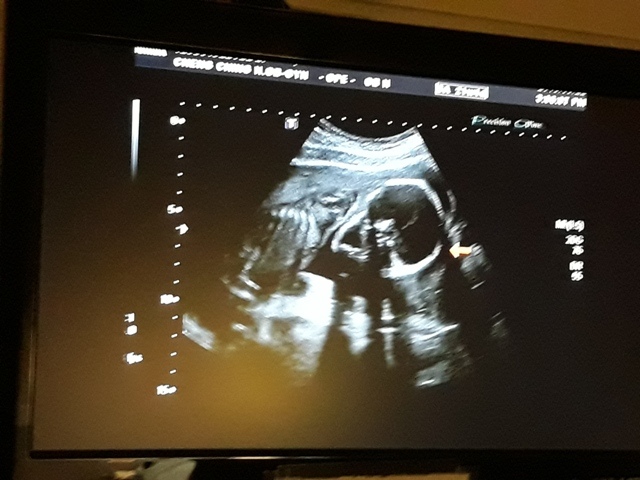

進到超音波室後,發現幫小純照超音波的就是關醫師(小純原本以為會是超音波技術員,照完才會有醫師來,結果是關醫師從頭照到尾)。關醫師一項一項的幫小飛做檢查,雖然是高層次的超音波,比平常的產檢還仔細,但是很多東西我和小純都看不太出來,但是手、腳的指頭和脊椎都很清楚。

檢查到外生殖器時,關醫師說『平平的』是女生,我和小純聽了都感到很訝異,上一次的產檢,關醫師不是說看到『凸凸的』是個男生,月中羊膜穿刺的報告出來之後,小純也有詢問打電話給他的人,也說是男生,怎麼性別翻盤了,小純跟關醫師說,羊膜穿刺的報告說是男的,關醫師說,既然羊膜穿刺的報告是男的,那就是男的沒錯,以羊膜穿刺的報告為準,超音波也有可能會因為角度的問題而誤判,後來關醫師照到小飛把腳打開的樣子,確定是男的。

今天的高層次超音波照下來,小飛還蠻健康的,唯獨FL(大腿骨的長度)的成長,比目前實際的天數(21週又5天)還小(超音波照出來是20週又6天),不過還在正常值內,小純聽到這個消息心情有些Blue,問關醫師多喝牛奶能不能改善,關醫師卻叫小純不要喝太多牛奶:「牛奶喝多了,會有牛脾氣。」關醫師也不只一次的表示,希望孕婦不要吃太多,吃太多會讓小寶寶變大,這樣不利於生產,至於FL成長比較慢的事,關醫師說,孩子出生再補給足夠的營養或者運動即可。